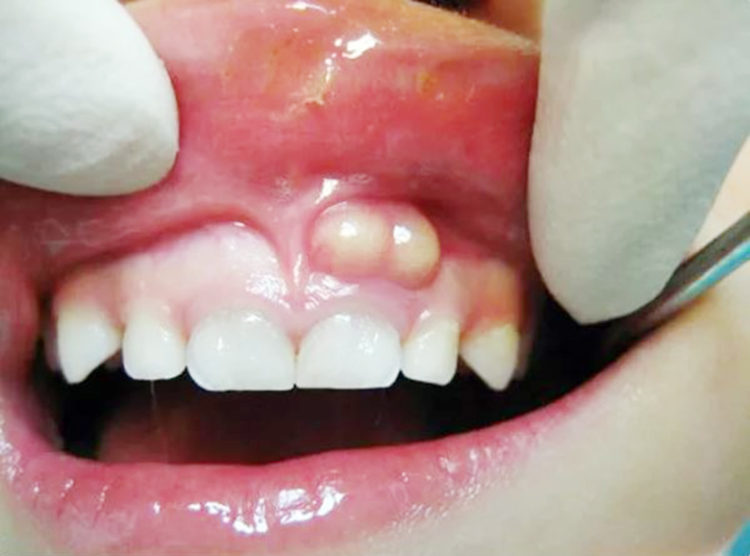

Nướu xuất hiện mụn mủ nhỏ, có thể chảy dịch.

Ban đầu, nang chân răng thường không gây đau nên nhiều người dễ chủ quan. Tuy nhiên, khi nang phát triển, bạn có thể gặp các dấu hiệu sau:

Sưng nhẹ vùng nướu hoặc mặt tại vị trí răng bị tổn thương.